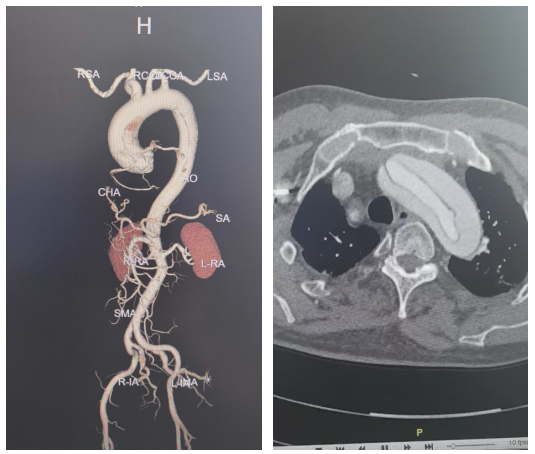

患者为73岁男性,因急性主动脉夹层入院。术前检查显示,夹层范围广泛,累及升主动脉、主动脉弓、降主动脉直至腹主动脉,并波及多支重要分支血管,手术复杂度高。

术中探查进一步证实病情进展,心包腔内可见约200ml血性积液,较术前影像明显加重,提示存在较高破裂风险。升主动脉明显扩张并呈蓝紫色,主动脉夹层形成明确。破口位于主动脉根部,距主动脉瓣右无交界上方约1cm,主动脉瓣启闭功能尚可。

在充分评估后,手术团队决定在传统标准升主动脉置换及全弓重建术式框架下,联合应用双分支型术中支架系统,以实现弓部及降主动脉的同步重建,从而在保证治疗完整性的同时优化整体手术流程。术中植入双分支术中支架系统,并将人工血管远端嵌套至支架近端人工血管内完成连接固定。恢复循环后心脏顺利复跳,完成无名动脉吻合并逐步复温,最终顺利停机,手术过程整体平稳。